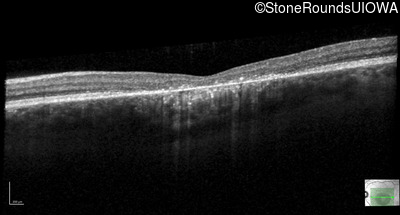

Age at visit: 17 years

OD OS

Age at visit: 17 years (Visit 2)

Age at visit: 21 years

Age at visit: 23 years

Age at visit: 25 years